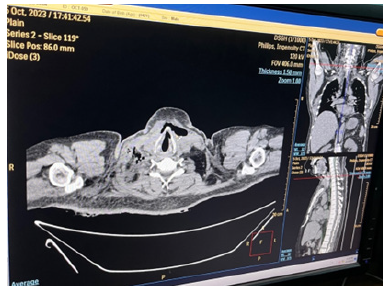

Chest radiograph showed slight widening of mediastinum. Blood for hemoglobin was 11.2gm%; total WBC count was 9.9 X109 /L (Neutrophils 88.1%, Lymphocyte 9.5%, Monocyte 2.4%); platelet count was 36 X109/L; ESR was 40mm per 1sthour; serum creatinine was 4.9mg/dl (0-1.3mg/dl); blood urea was 244.3mg/ dl (10-50mg/dl); serum sodium was 132 ; potassium was 4.4; chloride was 98; total bilirubin was 15.6 mg/dl (0.2-1.0mg/dl); Aspartate aminotransferase was 65U/L (9-48U/L); LDH was 502U/L (200-480U/L). Blood sugar (105.6mg%) and Hb A1 C were normal. Blood for retroviral serology was negative; serology for hepatitis B and C were negative. Computed tomography (CT) neck showed right cervical lymphadenopathy with some areas of break down suggestive of abscess. CT chest revealed features of mediastinitis and mediastinal abscess; they were in continuation with pre-tracheal fascia as seen in CT neck findings (Figures 2-12).

Figure 5: CT chest showing multiple abscess with surrounding opacities in the anterior mediastinum suggestive of mediastinitis and mediastinal abscess, and minimal left pleural effusion.

Figure 6: CT chest showing larger abscess in the anterior mediastinum with minimal left pleural effusion.

Figure 7: CT chest showing larger abscess with surrounding inflammation in the anterior mediastinum with minimal left pleural effusion.

Figure 9: CT chest showing mediastinitis and rounded opacity with air speck at the level of trachea bifurcation.